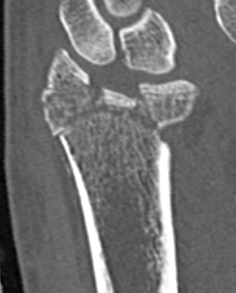

CT for further evaluation of articular congruency

Unacceptable reduction

1. Distal radial Step > 2mm

- leads to RC OA radiographically

- not proven to lead to dysfunction

2. Articular incongruency sigmoid notch / DRUJ > 2 mm

3. Radial shortening > 5 mm

- leads to ulnocarpal abutment

4. Radial inclination < 15o

5. Sagittal tilt

- > 15o dorsal

- > 20o volar

- +/- marked dorsal comminution